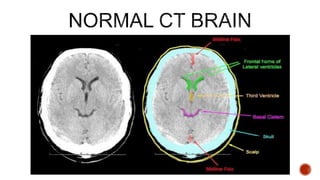

CT Scanners take a series

of head X-ray pictures from

all vantage points

360º around a patient's

head

The amount of radiation that

passes through, or is not

absorbed from, each angle

is digitized & entered into a

computer

When viewed in sequence, the

images allow mental

reconstruction of the structure

of the brain

The computer uses matrix algebra

calculations to assign a specific density

to each point within the head & displays

these data as a set of 2-D images

TISSUE APPEARANCE

BONE WHITE

CALCIFIED TISSUE WHITE

CLOTTED BLOOD WHITE

GREY MATTER LIGHT GREY

WHITE MATTER MEDIUM GREY

CSF NEARLY BLACK

WATER NEARLY BLACK

AIR BLACK